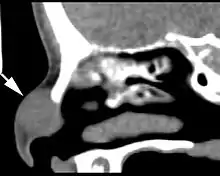

Imaging findings

Imaging studies are performed before surgery or biopsy to preclude an intracranial connection. Images usually show a sharply circumscribed but expansile mass. It may be difficult to exclude the intracranial connection if the defect is small whether employing computed tomography or magnetic resonance.[2]